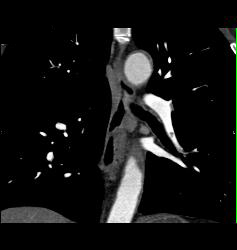

Pulmonary Embolism (PE) in Left Lobe Lung